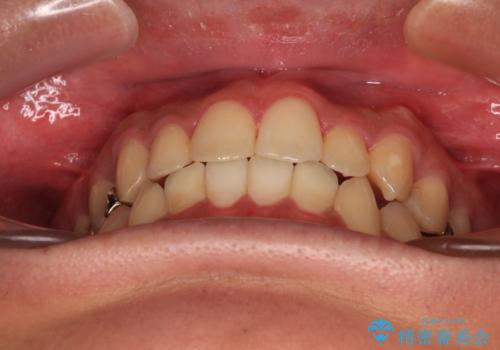

前歯のクロスバイト インビザラインによる矯正治療

- 上下のクロスバイトと前歯のデコボコを気にして来院された患者様です。

インビザラインを用い、IPR(歯と歯の間を削る)と歯列全体を拡大させることで、歯並びを整えていくこととしました。

インビザライン特有の、治療後半に奥歯が咬み合わないという事象が長引きました。

咬み合わないときの対処方法は色々とありますが、ゴムかけなどを活用して噛めるようにしました。